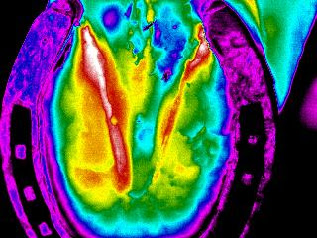

Este aumento de temperatura en el miembro posterior izquierdo, resultó ser un desgarre

muscular.

Absceso en zona plantar del casco